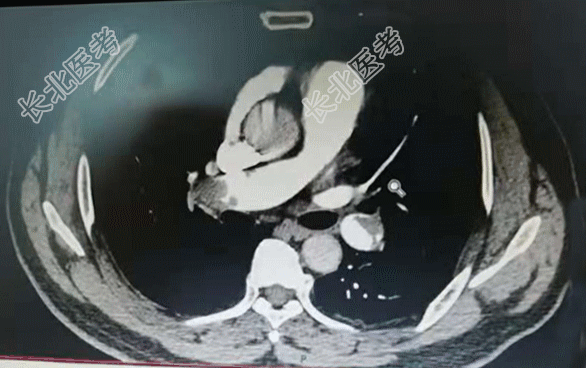

【现病史】2天前,患者无明显诱因出现右侧胸痛不适感,伴呼吸费力。当时无咳嗽、咳痰、发热等症状。以为是劳累导致的症状,经休息后症状缓解不明显,今晨起疼痛症状加重,家属拨打120急救送入我院,急诊科查指脉氧98%,行肺部CTA检查时指脉氧降至92%,肺部CTA显示:肺栓塞。诊断为:肺栓塞。发病以来饮食、睡眠差、小便正常,大便未解,体重无明显变化。

【辅助检查】肺部CTA显示:肺栓塞。心电图:标3、Avf、V₄-V₆导联T波改变。